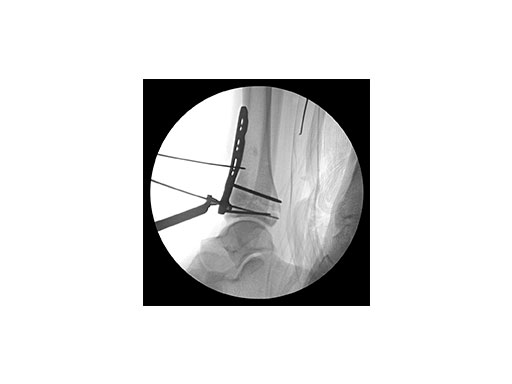

A 45-year-old patient fell from his horse, receiving a closed bimalleolar fracture/ dislocation (Fig 10). Computed tomorgraphy demonstrated an additional anterolateral avulsion injury and syndesmosis dislocation. Osteosynthesis was conducted with a VA-LCP Lateral Distal Fibula Plate.

Push technique was required to achieve fibular reduction, and the syndesmosis was reduced and clamped with periarticular clamps (Fig 11). Postoperative x-rays at 4 weeks demonstrated good maintenance of reduction (Fig 12).